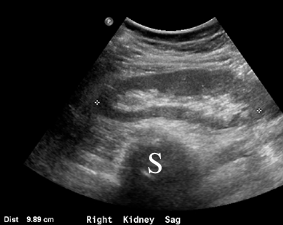

This is a sagittal image of the right kidney, with calipers on the image to measure the length of the organ from top to bottom. The spine (S) is the black area at the bottom of the image. The kidney has an outer dark grey part (called the cortex) surrounding a bright white, echogenic area (called the renal sinus).